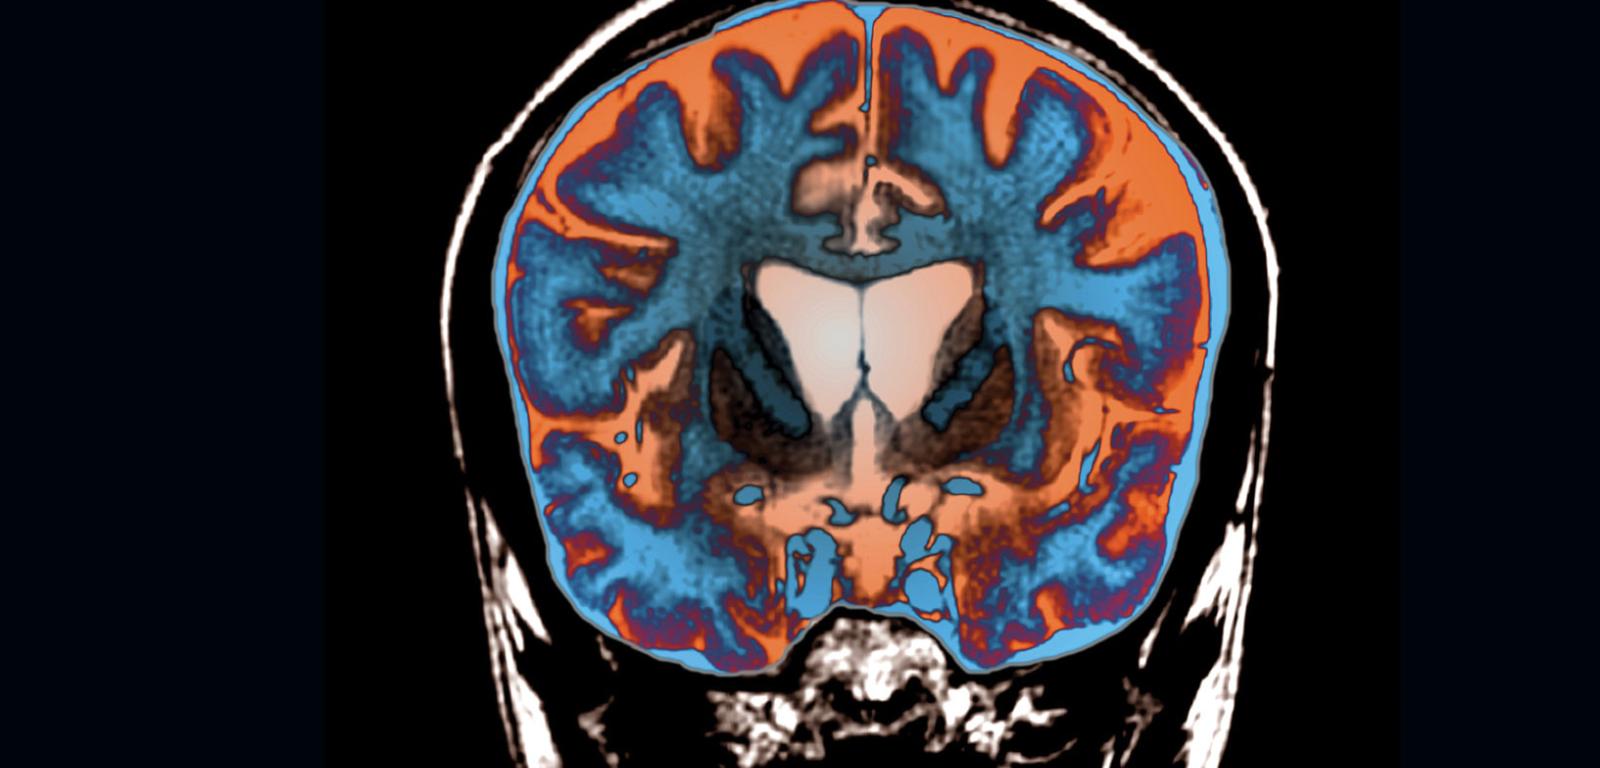

Badanie metodą jądrowego rezonansu magnetycznego, uwidaczniające zanik mózgu typowy dla choroby Huntingtona, potencjalnie możliwy do spowolnienia dzięki nowej terapii. Badanie metodą jądrowego rezonansu magnetycznego, uwidaczniające zanik mózgu typowy dla choroby Huntingtona, potencjalnie możliwy do spowolnienia dzięki nowej terapii. Zephyr/Science Source